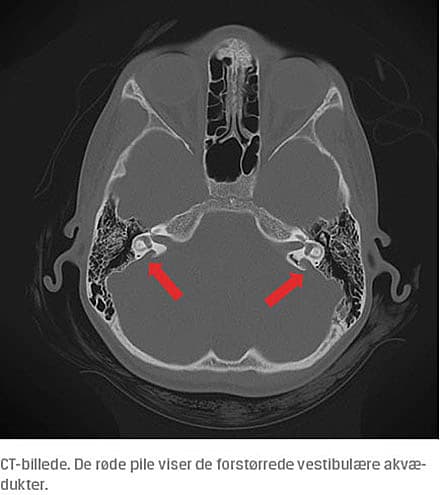

EVAS diagnostiseres radiografisk, når den anteroposteriore diameter af den vestibulære akvædukt på en CT-skanning måles til over 1,5 mm (målt mellem crus communes og udmundingen). Det anbefales, at patienter med EVAS undgår kontaktsport og anden aktivitet, som øger risikoen for hovedtraumer [3]. Et cochlearimplantat er fundet at være en god behandlingsmulighed, som øger både høre-, tale- og sprogudviklingen hos børn med EVAS.

Der blev foretaget en MR-skanning af cerebrum, hvorved man konstaterede, at der var FVA, der var uændret siden 2013. Dette blev bekræftet med CT af os temporale, hvor den største diameter blev målt til 4 mm på venstre side.